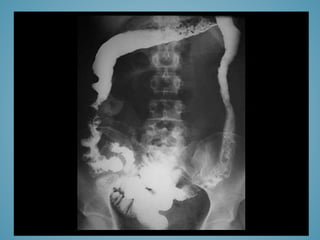

Barium enemas and radiological studies

- In ulcerative colitis its not diagnostic but suggestive

and shows :

- fine mucosal granularities

- superficial ulcers

- pipe stem appearance due loss of haustrations

- In crohn disease radiologic studies are necessary for

the entire GI tract ,,, plain films , enemas and contrast

small bowel follow through may show :

- Ulceration

- Narrowing

- Stricturing